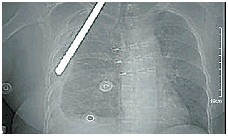

15点50分,救护车停在急诊科门口,黄女士被迅速移到抢救室。尽管每年抢救的病人不计其数,但像黄女士这样的伤者,很多医护人员还是第一次见。急诊外科张代福医生告诉记者,黄女士当时精神差、表情痛苦、全身湿冷、血压只有75\48mmHg。初步检查发现,金属螺纹钢从她右侧胸部穿入,贯穿体内,从左侧面部穿出。“这么粗的钢筋贯穿身体,会经过体内多个重要脏器及大血管,可能致重要脏器的损伤及大血管破裂,从而引起大出血甚至休克死亡。”

经CT检查,金属螺纹钢从女子右侧胸部穿入,贯穿体内,从左侧面部穿出。

事后,医护人员对钢筋进行了测量:长56厘米。